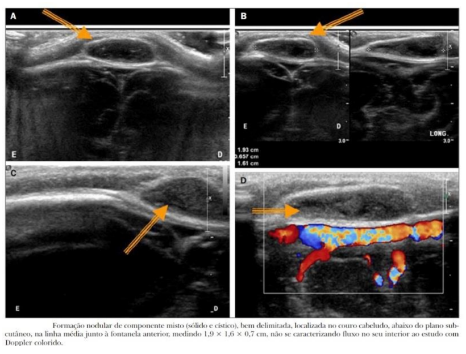

Paciente do sexo masculino, 10 meses de idade, com nódulo palpável no couro cabeludo na região mediana, junto à fontanela bregmática. Solicitada USG de couro cabeludo com o seguinte resultado:

Fonte: US nas lesões do couro cabeludo pediátrico / Diniz FV et al

Com base no resultado do exame, qual a principal hipótese diagnóstica: